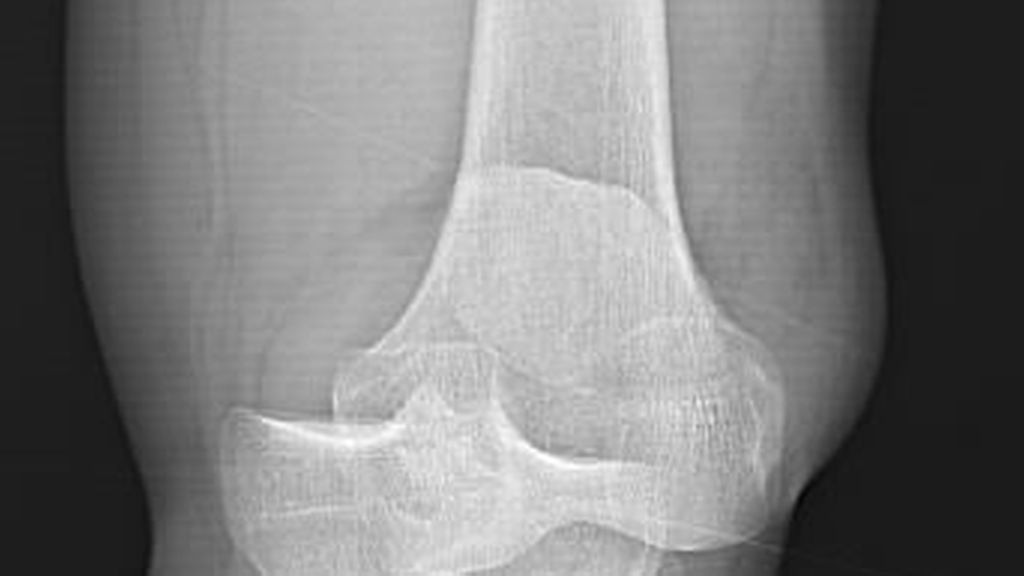

Diagnostik und Therapie der Kniegelenkluxation

Luxationen des Kniegelenks sind sehr seltene, aber schwerwiegende Verletzungen, die häufig mit Komplikationen einhergehen und unbehandelt zu schweren Instabilitäten im Knie führen können ...